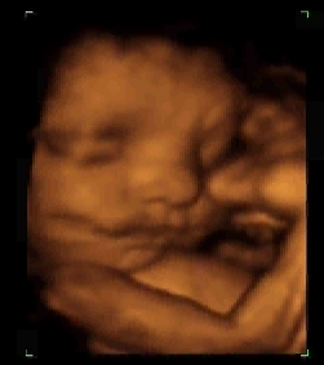

30 semanas y 5 días

Este feto tiene la mano ocultándose el ojo con el dedo pulgar de la mano derecha. Observe también como saca la lengua. ¿Se estará burlando del ginecólogo? Observen una pequeña sombra delante de la boca, no es que tenga bigote, es que tiene el cordón umbilical.